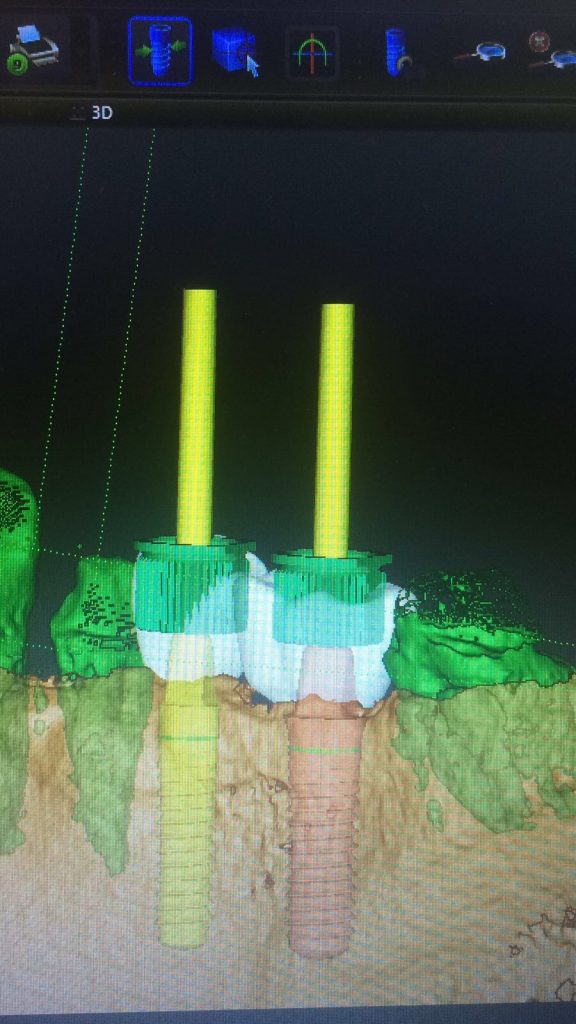

Autores: PRÓLOGO Asimismo, desde el punto de vista pedagógico, el profesional nobel en la materia tiene a su alcance la posibilidad de corregir cualquier posición implantaría en el ordenador, planear los provisionales y plasmarlos en la bio réplica antes de tocar al paciente a operar. Todos estos razonamientos nos llevan a presentar un caso de condiciones muy favorables para poner en práctica estos métodos como primer acercamiento a una Odontología Digital de alta calidad, con medios informáticos, que ya están presentes en la profesión de hoy en día, y será la protagonista única del futuro. Por otro lado, después de numerosos estudios que nos llevan a plantear el “gap” entre implante y pilar(abuttment), como principal responsable de la periimplantitis dado que la microbiota presente en el mismo es imposible de limpiar y en su presencia la cortical ósea reacciona reabsorbiéndose, nos ha llevado a utilizar implantes monobloc ya que los ejes implantarios y protéticos coincidían, y nos permitían su uso. Además, el circonio, ha mostrado a la luz de estudios muy recientes, una preservación y adhesión de los tejidos blandos superiores al titanio, tanto en su tratamiento de superficie de la rosca como a nivel gingival. DESARROLLO Paciente varón de 68 años, con antecedentes de radio/quimioterapia cinco años antes, con Rehabilitación Oral de los cuatro cuadrantes, con una Oclusión Mutuamente Compartida conservada, (REF.8) la que fracasa en el cuadrante 4, 19 años después. El mismo presentaba un puente de porcelana sobre circonio con pilares en 44 y 47, reemplazando el edentulismo de 45 y 46. Se produce la fractura del PM del 44, y ante una endodoncia antigua y corta, se decide implantar las zonas edéntulas, conservando temporariamente los pilares, hasta producida la oseointegración, para entonces también exodonciar el 44. DIAGNÓSTICO Tomamos impresiones del maxilar antagonista, Arco Facial Estático y realizamos montaje del mismo mediante la sistemática ARTEX. Producimos la relajación del músculo Pterigoideo Externo, para obtener la ORC (Oclusión en Relación Céntrica) mediante el método de Laminillas de Long, basado en el concepto de INERVACIÓN RECÍPROCA. Esto nos permitirá montar el maxilar inferior, tanto en su forma de: La primera para practicar la cirugía guiada y comprobar su eficacia, y el modelo de yeso para ser escaneado y confeccionar la GUÍA QUIRÚRGICA. La Biorréplica la obtenemos transformando los archivos DICOM que nos da el CBCT en archivos STL, y a partir de ellos, mediante una tecnología de PROTOTIPADO RÁPIDO, la obtención de un objeto físico en 3D a través de la aglutinación selectiva de una sucesión de capas de polvo. Procedemos a montar la biorrèplica y el modelo de yeso del caso. Podemos verificar la exactitud de las medidas del hueso residual en la bio réplica y compararlas con el scanner. Arrojando un resultado de 8,5 mm de cortical externa a cortical externa. Pudiendo también medir la distancia hasta el dentario. y comparar gracias a la ventana lateral de la biorréplica Dándonos 22mm de distancia. Con lo cual deducimos que implantes de 4,1mm por 12 mm serán perfectamente rodeados de hueso. Medimos también la distancia desde oclusal del antagonista, hasta el hueso desnudo. Lo mismo que, mediante la utilización de la guía radiológica, con un material radiolúcido colocado en gingival de la misma, podemos medir la altura de la encía. Con lo cual podemos calcular la altura del pilar. Es entonces cuando con el programa COC Diagnostix se realiza la programación final: Obteniendo no solo la ubicación, largo, ancho y ángulo de los implantes sino también los provisionales mediante CAD CAM. Ya entonces podemos hacer la práctica quirúrgica en la bio réplica, mediante la guía quirúrgica, instalando los implantes de prueba que no serán los de circonio, ya que la casa no cuenta con ellos, pero si otros de las mismas dimensiones. TRATAMIENTO Entramos ya en la cirugía propiamente dicha. Antisepsia de la zona a operar y zonas anexas. Comprobación del perfecto ajuste e inmovilidad de la G.Q. en boca durante la cirugía. Marcado de la encía y perforación de la cortical. Visión a través de la Guía de la mínima intervención anterior. Comprobación sin Guía. Incisión mínima mesio distal, para apartar y conservar encía queratinizada. Secuencia de drills, perforando a profundidad requerida Observación del Mínimo Trauma Implantes Strauman de Zirconio Monoblock en blíster y montádo en contrángulo reductor. Instalación controlando torque con contrángulo reductor. Comprobación clínica. Comprobación Radiográfica y con Guía. Toma de impresiones, y armado de modelos con técnicas de pasividad protética. Montaje. Resultado de las provisionales ejecutadas por CAD CAM Al no estar conformes con el resultado decidimos desechar dichas provisorias y optar por repetirlas. Nuevas provisorias realizadas mediante encerado convencional. Estado de los tejidos blandos. Provisorias en boca. Oclusión de Estímulo Inmediato. Ref.10: Carga inmediata .Alberto y Diego Bechelli. Comprobación mediante CBCT post operatorio Componentes del equipo (En la próxima presentación, mostraremos las coronas definitivas de porcelana sobre circonio, y la desoclusión provocada por una OCLUSIÓN MUTUAMENTE COMPARTIDA, sobre estos implantes y otros seis mas) REFERENCIAS

FIG: 21-22-23-24-25-26

Fig. 21

Fig. 22

Fig. 23

Fig. 24

Fig. 25

Fig. 26